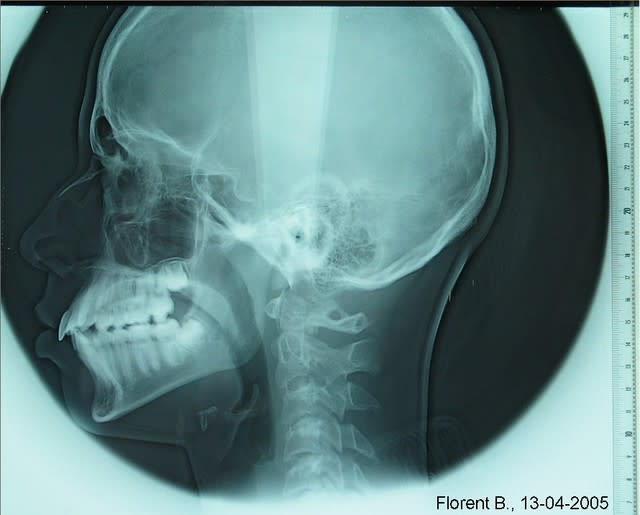

Voici la téléradiographie avec références millimétrées. Bon travail et encore merci pour votre aide.

050413b florent p3gsxj - Eugenol